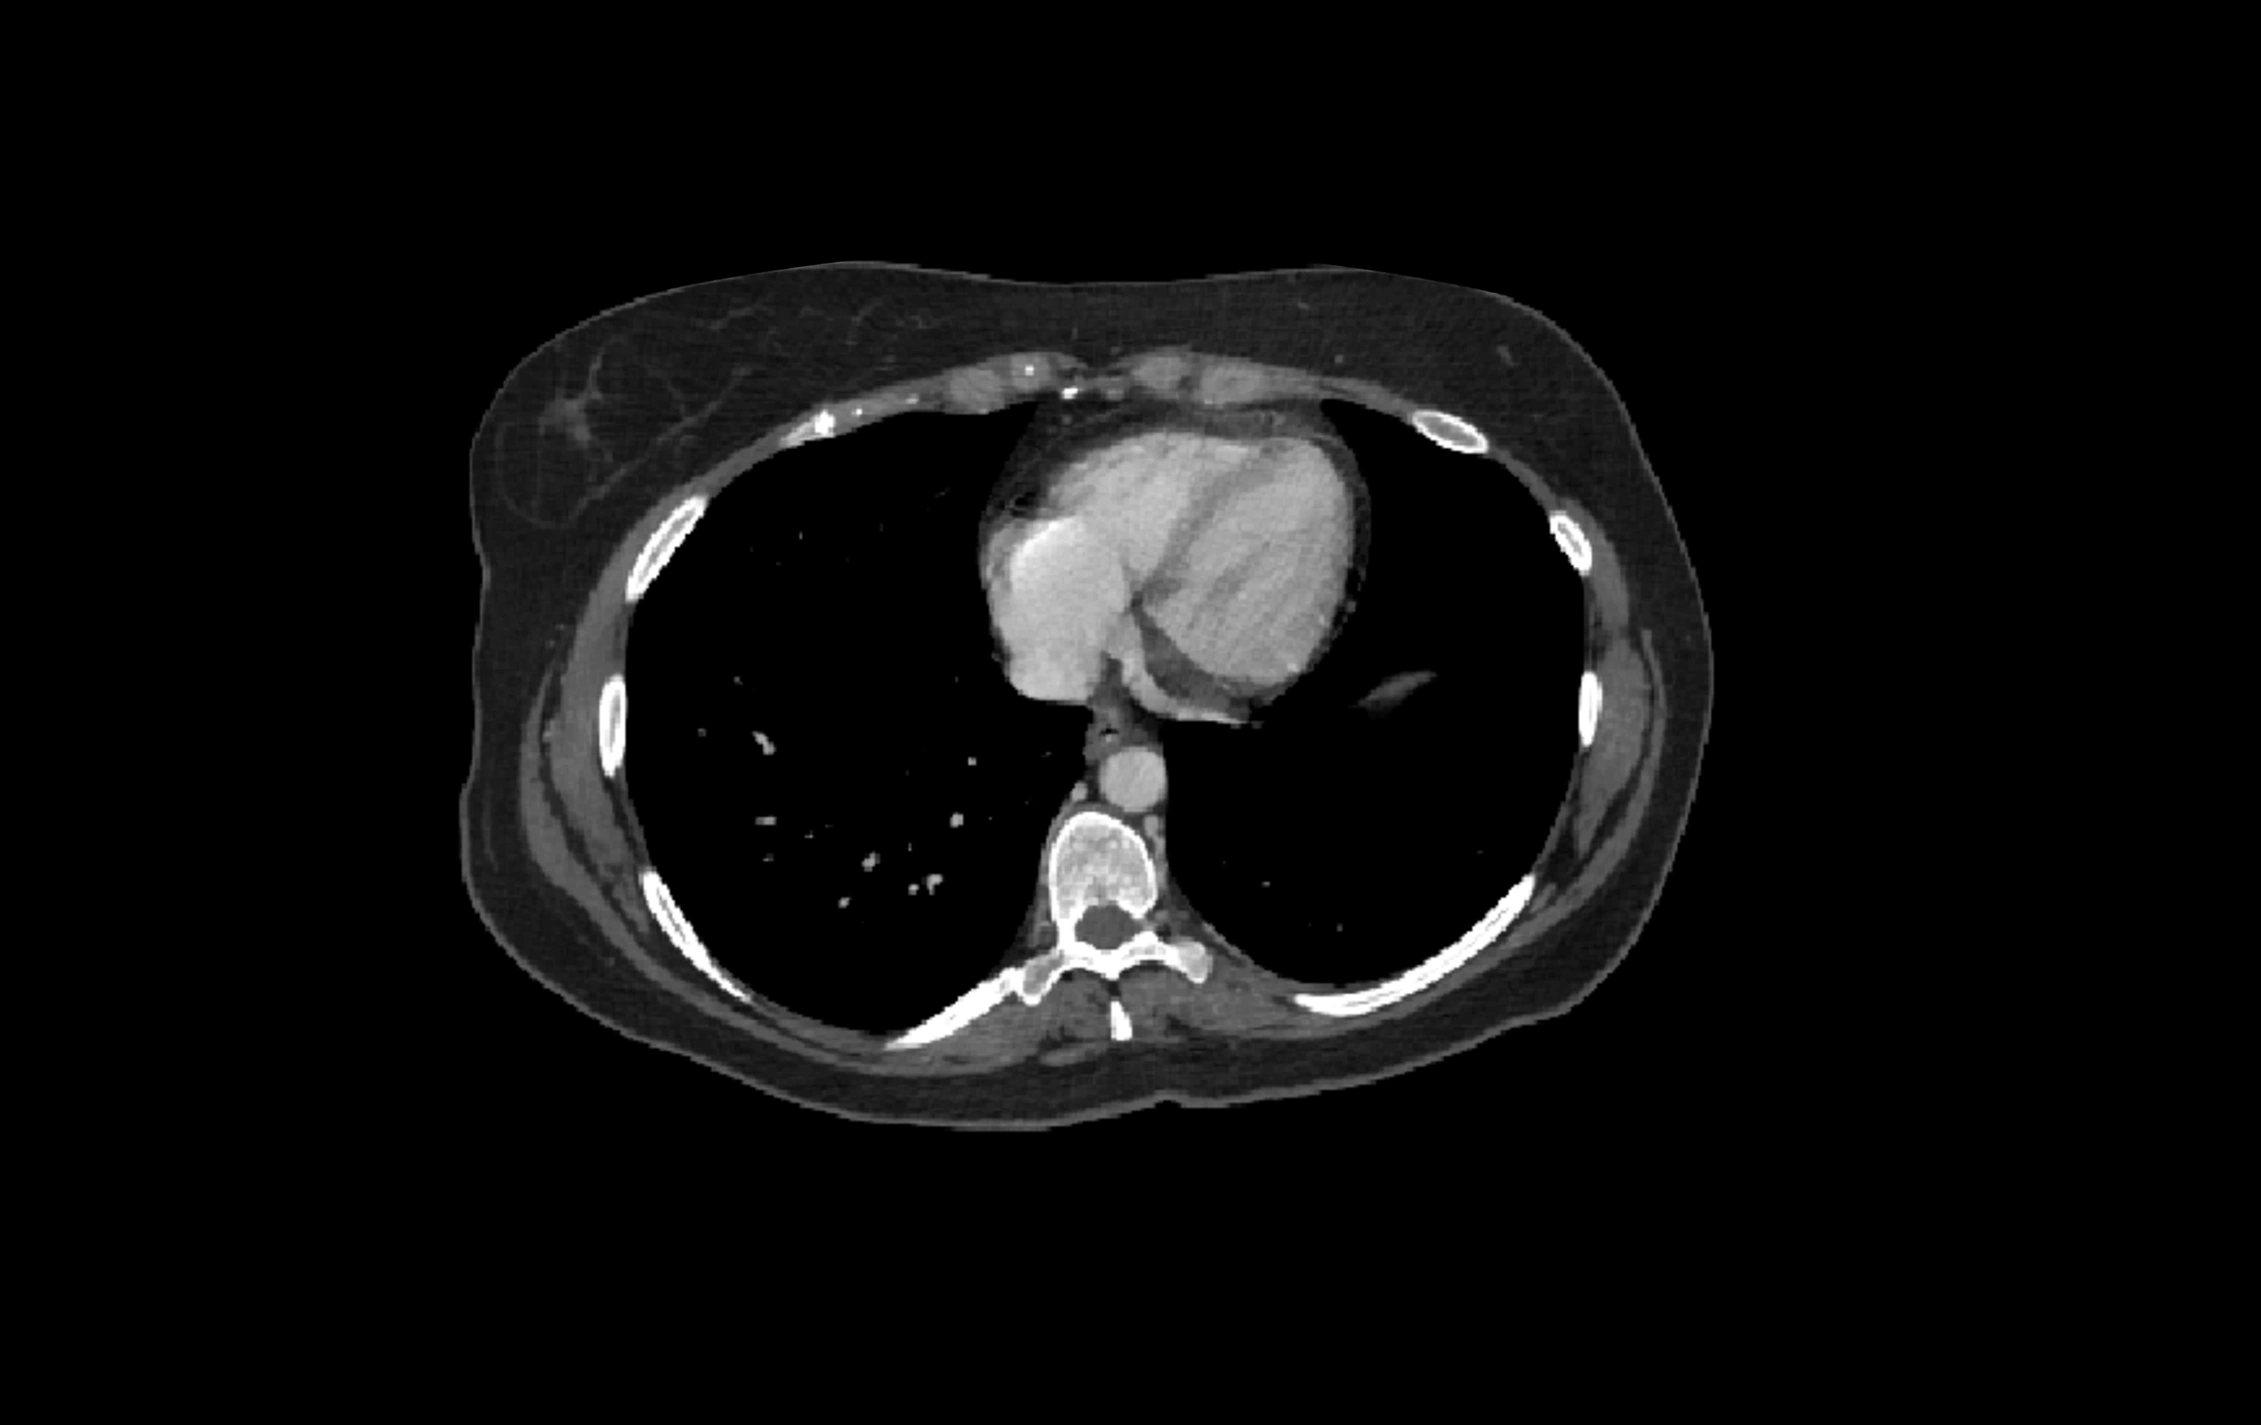

CT Image

image